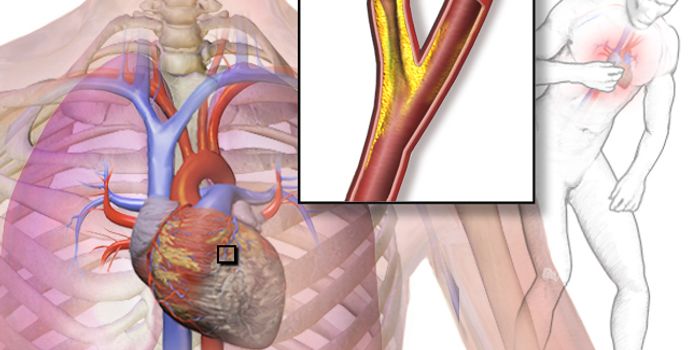

MAR 03, 2017CardiologyA new, non-invasive technique for detecting inflammation provides a unique opportunity for the early identification of a ...

NOV 07, 2017ImmunologyAs cardiac cells begin to die by the masses after a heart attack, the immune system kicks into action as if there were a ...

FEB 09, 2017CardiologySometimes a heart attack leads to heart failure later in life, and sometimes it doesn’t. Scientists are concentrat ...

DEC 07, 2020Cell & Molecular BiologyCNIC researchers have found that there is an autoimmune link to cardiovascular disease that may improve diagnostic and t ...

NOV 01, 2016CardiologyTwo interactive proteins were discovered in connection to atherosclerosis-related macrophage activation, according to a ...

JUN 09, 2017CardiologyA natural sugar called trehalose reduces plaques associated with atherosclerosis and heart disease by improving t ...